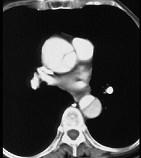

问题 男,64岁,突感胸部剧痛2h,呈撕裂样,并向背部放射,有高血压病史10年,含服硝酸甘油3片不能缓解,CT检查如图所示。首先应考虑的诊断是 ( )

选项 A、急性胸膜炎 B、急性心肌梗死 C、急性胆囊炎 D、急性胰腺炎 E、主动脉夹层

答案 E